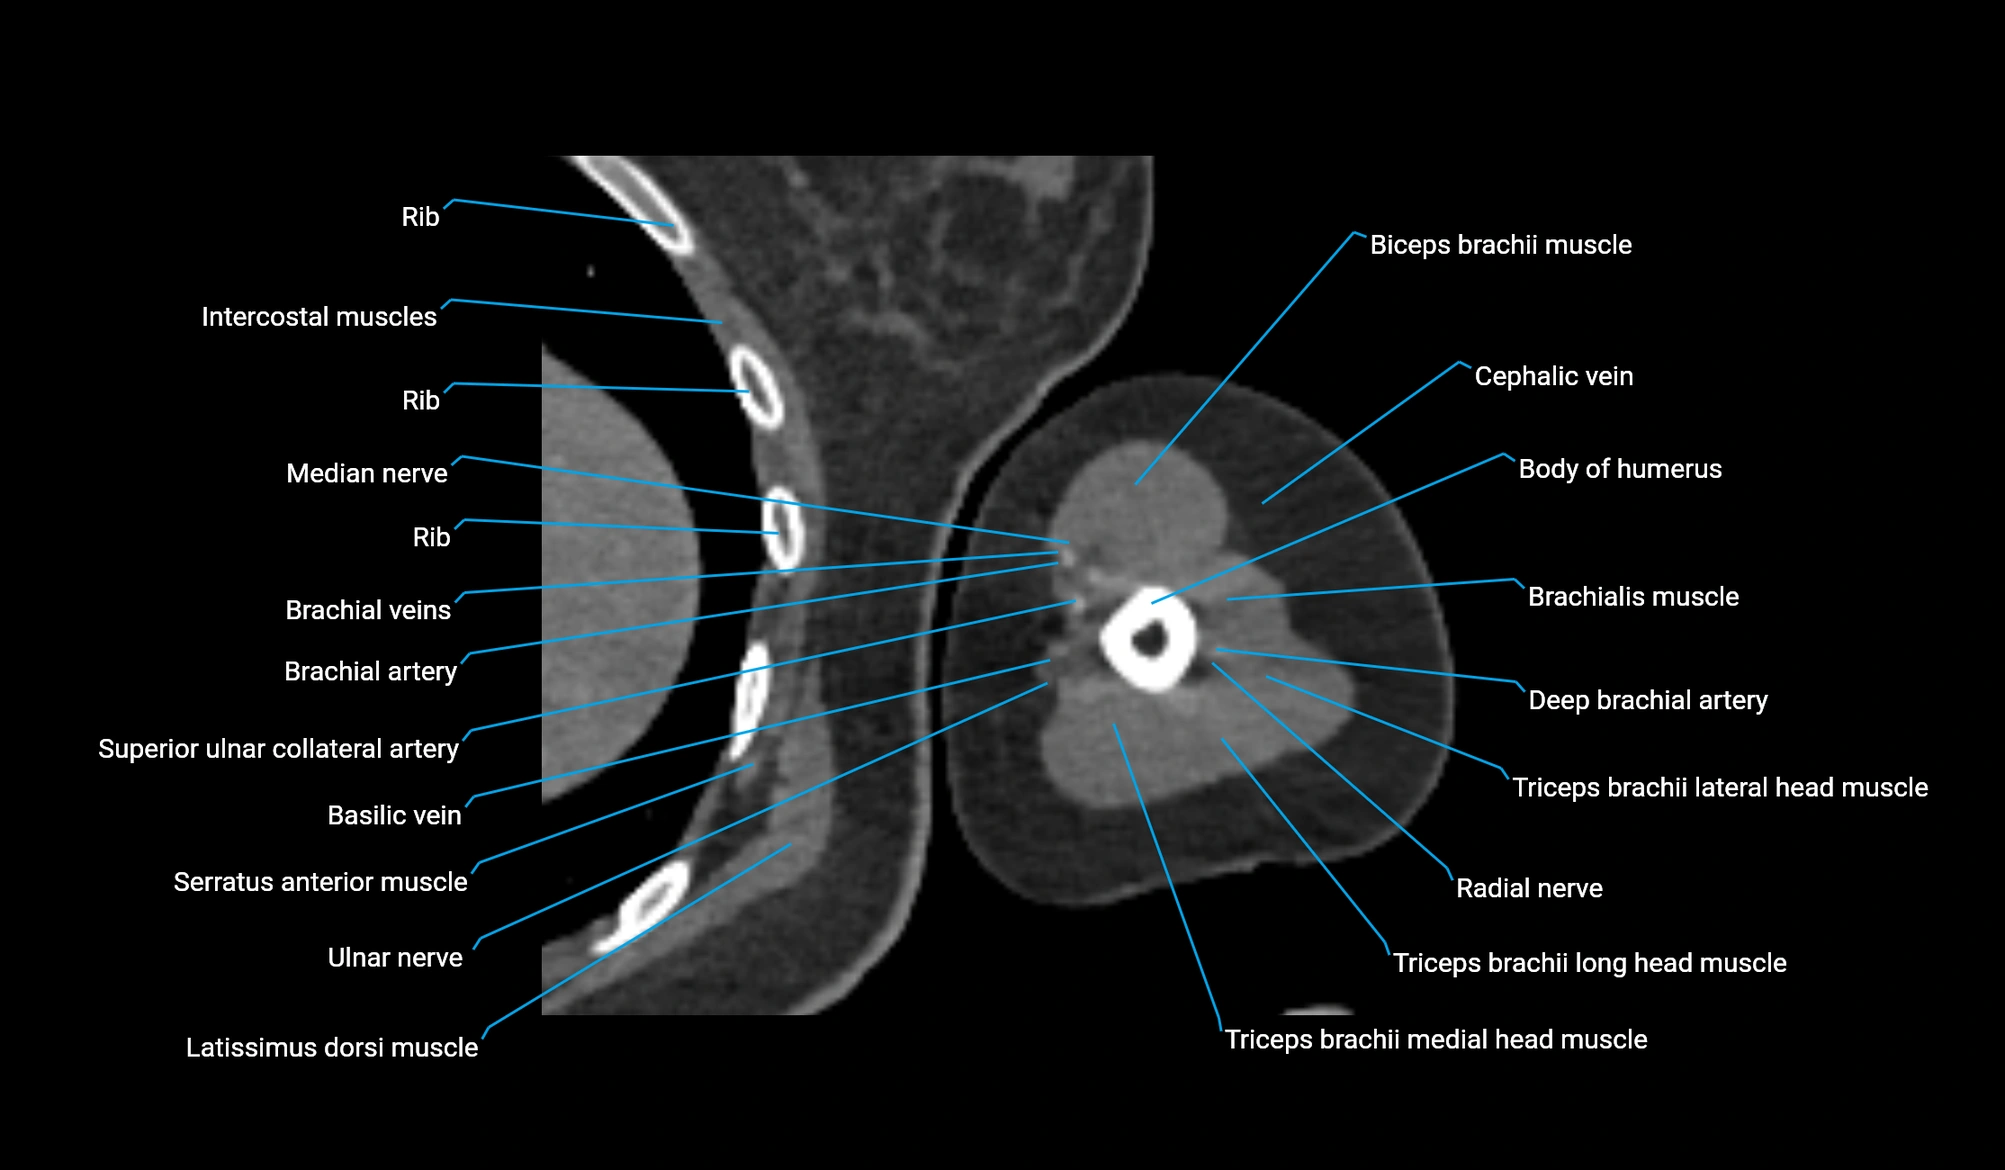

CT image